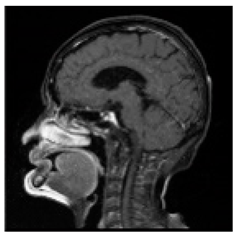

| Original Medical Images | |||||||

| Pair 1 | Pair 2 | Pair 3 | Pair 4 | ||||

![]() (1-9) PSNR = 44.14 | ![]() (1-10) PSNR = 41.90 | ![]() (1-11) PSNR = 40.09 | ![]() (1-12) PSNR = 41.41 | ![]() (1-13) PSNR = 42.24 | ![]() (1-14) PSNR = 40.35 | ![]() (1-15) PSNR = 40.79 | ![]() (1-16) PSNR = 40.84 |

| Shadow Images Produced by Using LSBs | |||||||

![]() (1-17) PSNR = 26.35 | ![]() (1-18) PSNR = 25.49 | ![]() (1-19) PSNR = 23.57 | ![]() (1-20) PSNR = 24.19 | ![]() (1-21) PSNR = 24.79 | ![]() (1-22) PSNR = 24.23 | ![]() (1-23) PSNR = 23.26 | ![]() (1-24) PSNR = 24.42 |

| Shadow Images Produced by Using Middle Bits | |||||||

![]() (1-25) PSNR = 18.97 | ![]() (1-26) PSNR = 19.95 | ![]() (1-27) PSNR = 14.10 | ![]() (1-28) PSNR = 13.84 | ![]() (1-29) PSNR = 16.66 | ![]() (1-30) PSNR = 13.23 | ![]() (1-31) PSNR = 13.38 | ![]() (1-32) PSNR = 14.75 |

| Shadow Images Produced by Using MSBs | |||||||